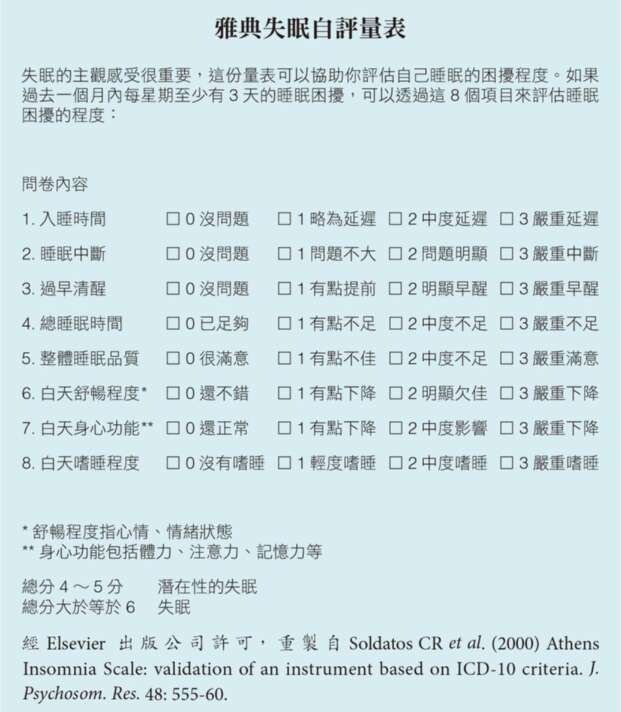

但無論如何,這3個詢問從現代醫學的角度來看,還是相當有代表性。比如說,在臨床上常用的雅典失眠自評量表 (Athens Insomnia Scale)透過8個和睡眠有關的詢問,來評估一個人整體的睡眠狀態。你也可以利用這個機會,先去回答這幾個問題,對自己睡眠的狀態做一個評估。根據專家的說法,如果得分有4到5分,可列為潛在性的失眠。總分大於等於6,也就是屬於失眠的族群。

我們注意看這8個問題,基本上還是不離前面所提到的這3個詢問,就算是第4個項目問到了總睡眠時間,也還是在問我們自己覺得夠不夠,並不是和一個具體的數字做比較。